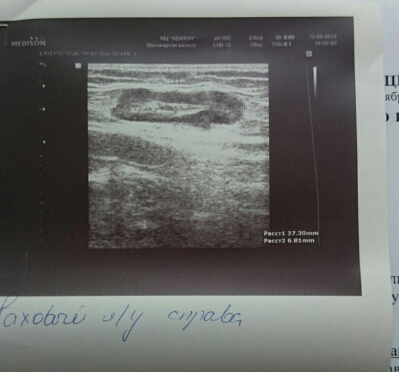

Узи, по щитовидке все нормально, внутренние органы добавился загиб желчного, не было такого, последнее узи делала в 12 недель, было все в норме. Ну и мои лимфоузлы, и фотка самого большого который на ноге. Врач сказала, что и Узи малого таза тоже покажет изменения, на эту процедуру пойду через два часа. На Узи вен записалась на вторник, настоятельно мне это рекомендовали, чтобы исключить тромбоз

- Вложения

-

- PicsArt_1410513048949.jpg (68.62 КБ) 638 просмотров

- PicsArt_1410513000805.jpg (128.35 КБ) 638 просмотров

- PicsArt_1410513076215.jpg (93.7 КБ) 638 просмотров